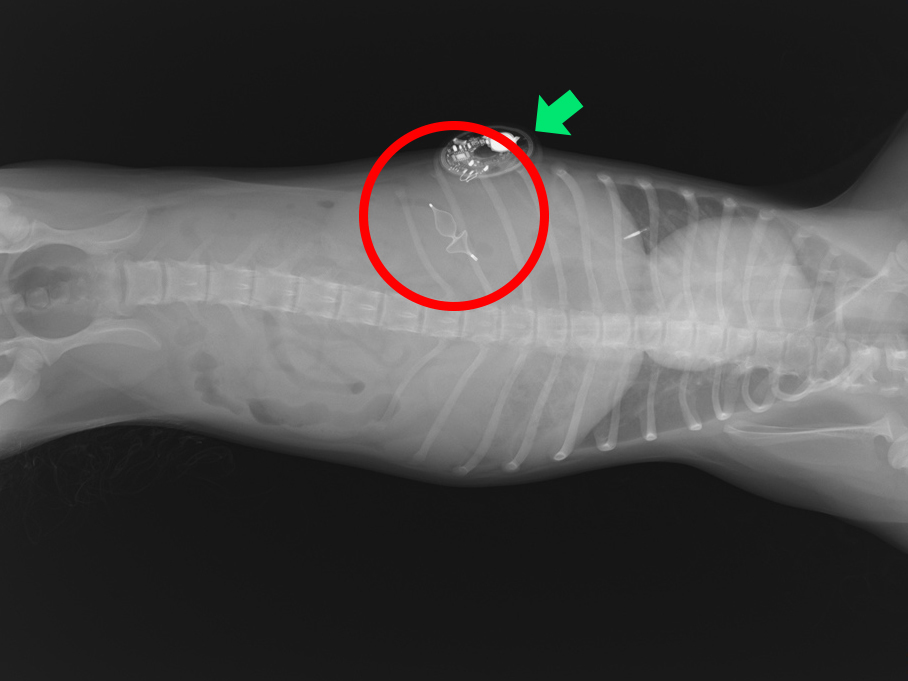

術後のレントゲン画像(赤丸がプラグ、緑矢印は血糖値の測定装置)